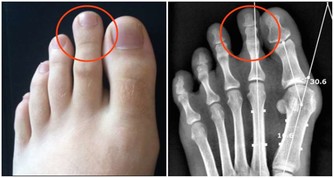

脾臟,脾臟切除本身疾病不會影響人的生命,但由於其參與消化及免疫系統,感染風險會增加,所以整體壽命多少會受到影響。